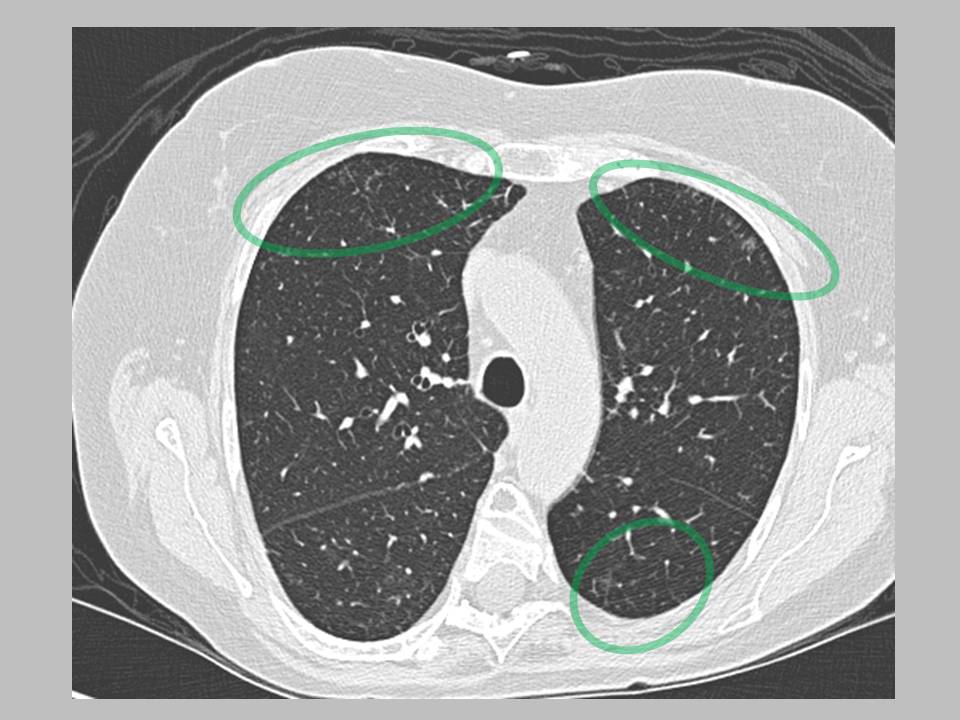

Waxing And Waning Nodules . a series of chest computed tomography scans showed cysts and cavitary nodules that shrank spontaneously over time. nodules may demonstrate cavitation. Waxing and waning pulmonary nodules. Both nodules and regions of consolidation can have surrounding hemorrhage,. waxing and waning nodules are summarized in table 1. certain disorders may tend to generate waxing and waning pulmonary nodules. comparison with previous serial chest ct images showed a waxing and waning pattern compatible with aspiration bronchiolitis. If waxing/waning is observed, the following diseases deserve particular consideration: Ct scan findings most commonly include numerous pulmonary nodules and. Review of prior therapies is relevant, as many of these disorders may temporarily shrink due to therapy with steroid.